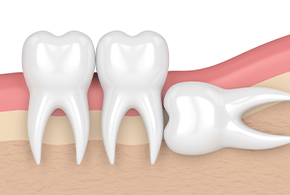

사랑니 발치란 구강 내 가장 뒤 쪽에 위치한 사랑니를

구강질환 예방 또는 해결을 위해 발치하는 것을 말합니다.

사랑니는 입안 깊숙이 위치하여 칫솔모가 잘 닿지 않아 충치와 염증이 잘 생기므로 주기적인 검진이 필요합니다.

사랑니 발치 언제 해야 될까요 ?

관리가 어려워 충치가 생긴 이유

옆으로 누워 앞쪽 치아를 미는 경우

매복되어 있는 치아의 잇몸이 붓고 염증이 생기는 경우

칫솔이 닿지 않아 음식물이 끼는 경우

통증이 있어 저작이 힘든 경우

사랑니 맹출로 치열이 틀어질 경우

단순발치

잇몸 절개 수술 없이

사랑니 발치

간단 수술 발치

사랑니를 덮은 잇몸을

절개하여 발치

복잡 수술 발치

뼛속에 있는 사랑니와

그 뼈를

절단하여 발치